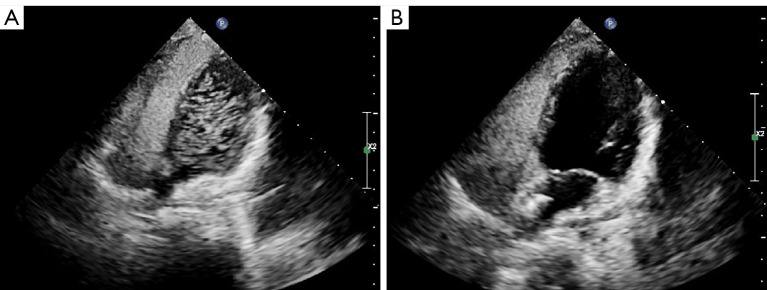

Results: All 46 children with PFO had severe migraine preoperatively. The PFO was determined by transthoracic echocardiography (TTE) and right heart contrast echocardiography suggested the presence of a significant right-to-left shunt (RLS). No residual shunt and complications were observed in all the children after intervention. Before PFO closure, every child experienced repeated migraines. Follow-up data for all patients were obtained by telephone, WeChat, or outpatient visits at 1, 6, 12, and 24 months after PFO closure. The migraine was significantly alleviated in 43 children, while three others experienced no change. There was a significant reduction in the frequency, duration, Visual Analogue Scale (VAS) score and Headache Impact Test-6 (HIT-6) score after PFO closure.